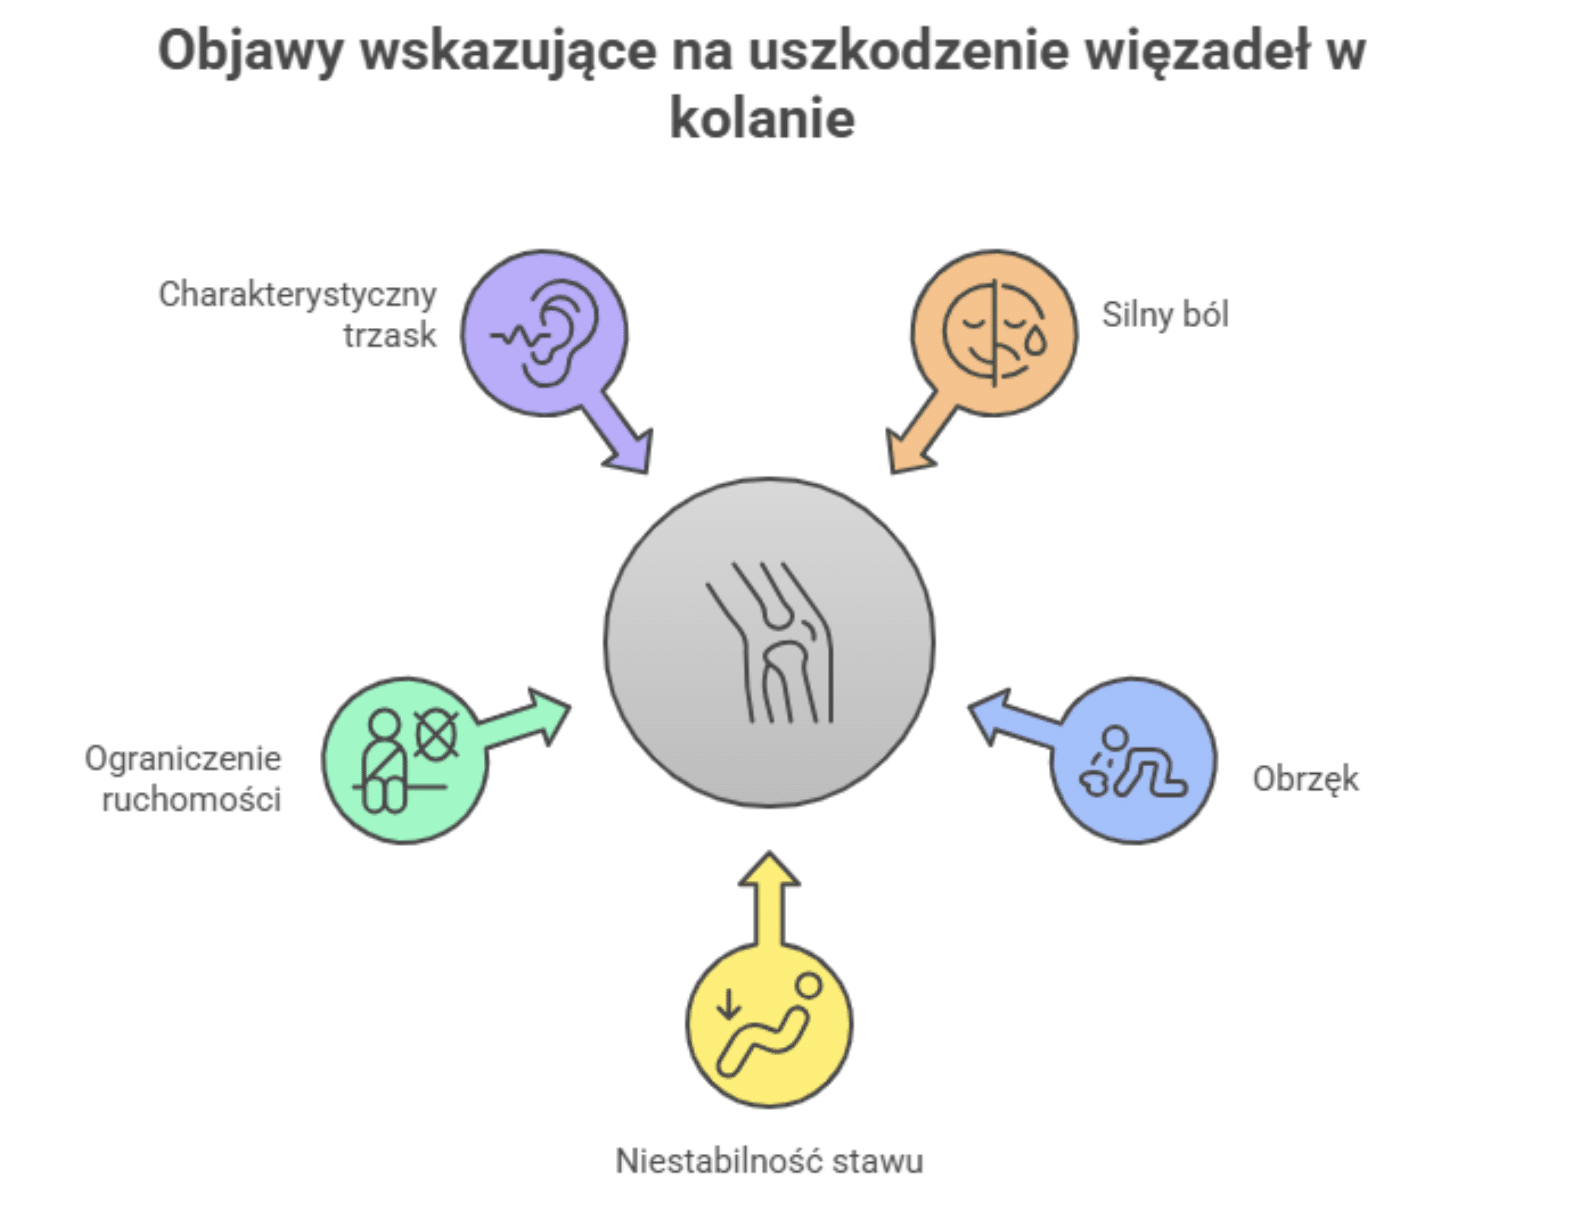

Rozpoznanie uszkodzenia więzadeł w kolanie nie zawsze jest oczywiste, jednak istnieje kilka charakterystycznych objawów, które mogą wskazywać na poważny uraz.

Silny ból pojawia się zazwyczaj natychmiast po incydencie. Może być ostry, przeszywający i uniemożliwiać dalsze obciążanie kończyny. W wielu przypadkach ból nasila się przy próbie poruszania stawem lub podczas chodzenia.

Bardzo często już w ciągu pierwszych godzin po urazie rozwija się obrzęk, który wynika z krwawienia do wnętrza stawu. Obrzęk może być znaczny i prowadzić do widocznego powiększenia kolana oraz uczucia napięcia skóry. U niektórych osób pojawia się również krwiak lub zasinienie w okolicy stawu, co świadczy o uszkodzeniu naczyń krwionośnych.

Kolejnym alarmującym objawem jest niestabilność stawu. Pacjenci często opisują to jako wrażenie „uciekającego” lub „rozchodzącego się” kolana, szczególnie podczas próby stania czy chodzenia. Może towarzyszyć temu uczucie braku kontroli nad ruchem kończyny dolnej. W przypadku całkowitego zerwania więzadła krzyżowego przedniego (ACL) niestabilność jest bardzo wyraźna i uniemożliwia bezpieczne poruszanie się.

Ograniczenie ruchomości to kolejny sygnał ostrzegawczy. Zakres zginania i prostowania kolana zostaje wyraźnie zmniejszony, a każdy ruch może powodować dodatkowy dyskomfort. W niektórych przypadkach pacjenci słyszą lub czują charakterystyczny trzask w momencie urazu, co często wiąże się z przerwaniem włókien więzadła.

Należy pamiętać, że objawy różnią się w zależności od stopnia uszkodzenia:

- Naciągnięcie więzadła: ból i lekki obrzęk są zwykle umiarkowane, a funkcja stawu pozostaje częściowo zachowana. Ruchy mogą być ograniczone, ale nie dochodzi do całkowitej utraty stabilności.

- Naderwanie więzadła: występuje silniejszy ból oraz wyraźniejszy obrzęk, pojawia się trudność z pełnym obciążeniem nogi i większe ograniczenie ruchomości.

- Zerwanie więzadła: objawy są najbardziej nasilone – ból jest bardzo intensywny, obrzęk narasta szybko, a niestabilność uniemożliwia normalne funkcjonowanie. Często dochodzi także do odgłosu trzasku w chwili urazu oraz znacznego ograniczenia ruchu.